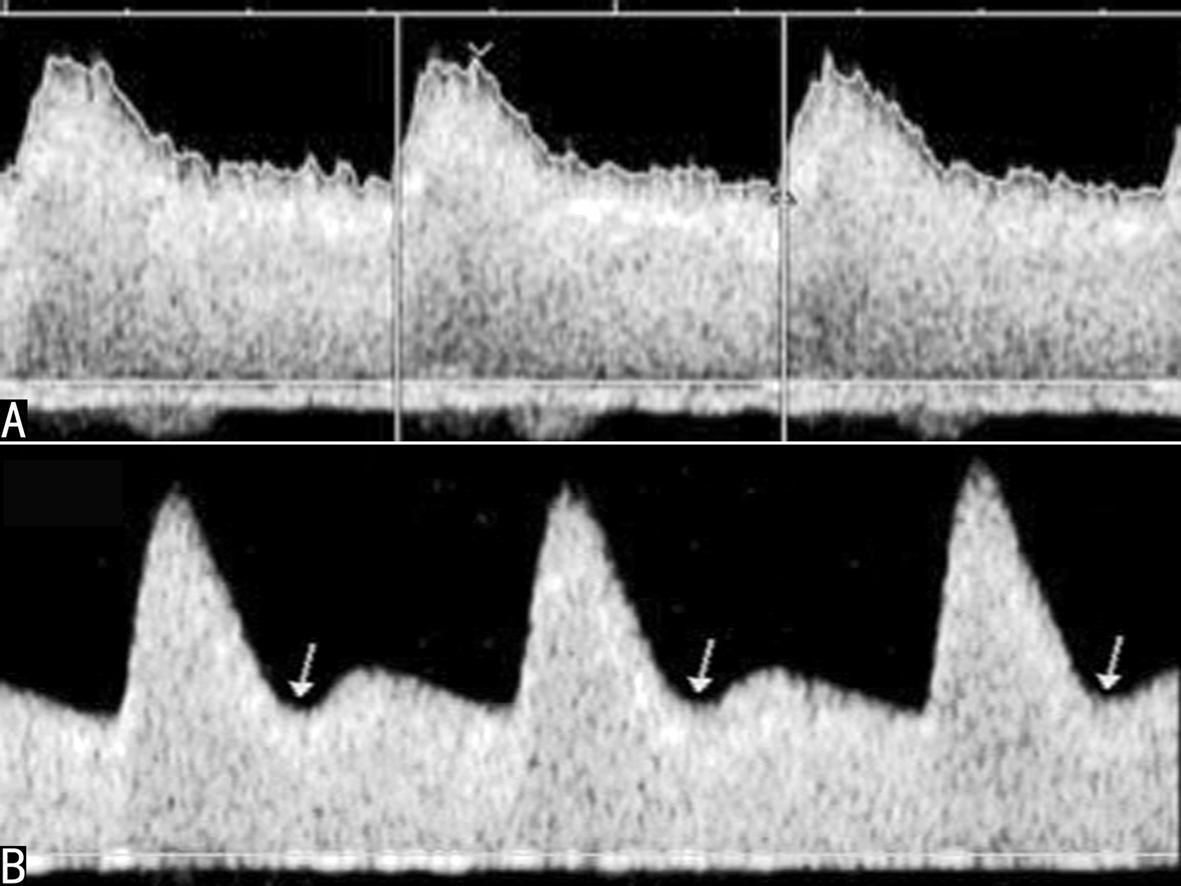

检查时需要注意部分孕妇的双侧子宫动脉血流速度曲线在舒张早期会显示一个向下的凹陷,称为舒张早期切迹(PN)(图5)。曾经认为子宫动脉血流速度曲线的舒张早期切迹与不良妊娠过程有一定的关系,但Gomez等在他们的研究中发现PN在整个妊娠期都可能出现,但愈到晚期PN的发生率越低,11~14周时发生率为46.3%,15~24周发生率为16.5%,24周至足月其发生率为5%。Souza等观察使用硫酸镁治疗严重的产前子痫病人时可以明显改善孕妇的子宫动脉PI,降低孕妇心率,但对PN没有明显的影响。提示某些病人PN的存在并不意味着都会伴发病理性变化,而子宫动脉PI的变化或二者结合可能更有意义。

图5妊娠期子宫动脉血流速度曲线的比较

A:妊娠中晚期正常子宫动脉血流速度曲线

B:妊娠期子宫动脉血流速度曲线的舒张早期切迹(箭头)